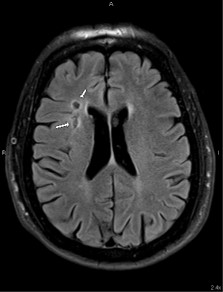

In the emergency room, his vitals indicated hypertension, with otherwise stable parameters. His EKG showed normal sinus rhythm at 73 bpm with an incomplete left bundle branch block. Carotid Doppler and CT angiography of the neck revealed 69% stenosis of the left carotid artery as shown in Figure 1 above, and less than 20% stenosis of the right carotid artery (Figure 2). He was started on Plavix and maintained on oral doses.

Figure 1: Showing a 69% stenosis of the left carotid artery with high flow velocity.